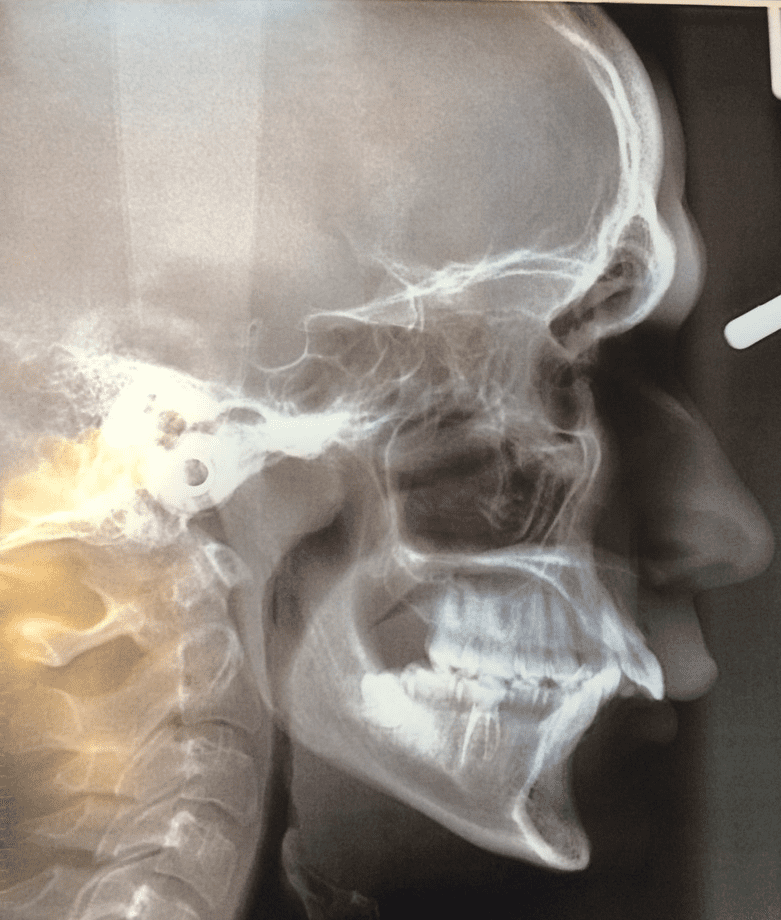

В пояснении к статье 56 Расписания болезней сказано: "...при аномалии прикуса II и III степени с разобщением прикуса более 10 мм (без учета жевательной эффективности) заключение о категории годности к военной службе выносится по пункту "б". У вас имеется сагиттальная щель 18 мм. Сагиттальная щель и разобщение прикуса - это одно и то же.

Но есть проблема: врач видимо забыл изначально указать размер сагиттальной щели и дописал его потом более мелким шрифтом в том месте, которое я обвёл красной рамкой:

Из-за этого со стороны военкомата могут возникнуть ложные обвинения - якобы вы сами дописали размер сагиттальной щели в уже написанное врачом предложение. Если бы размер сагиттальной щели был продублирован в формулировку диагноза, то проблем бы с этим не было, но там написано:

Без указания размера сагиттальной щели. Так что тут как повезёт: в военкомате могут не обратить на это внимание, а могут и обратить. В крайнем случае попросите, чтобы вас отправили к тому же самому врачу переписать заключение с изначальным указанием размера сагиттальной щели как в данных объективного исследования, так и в формулировке диагноза.